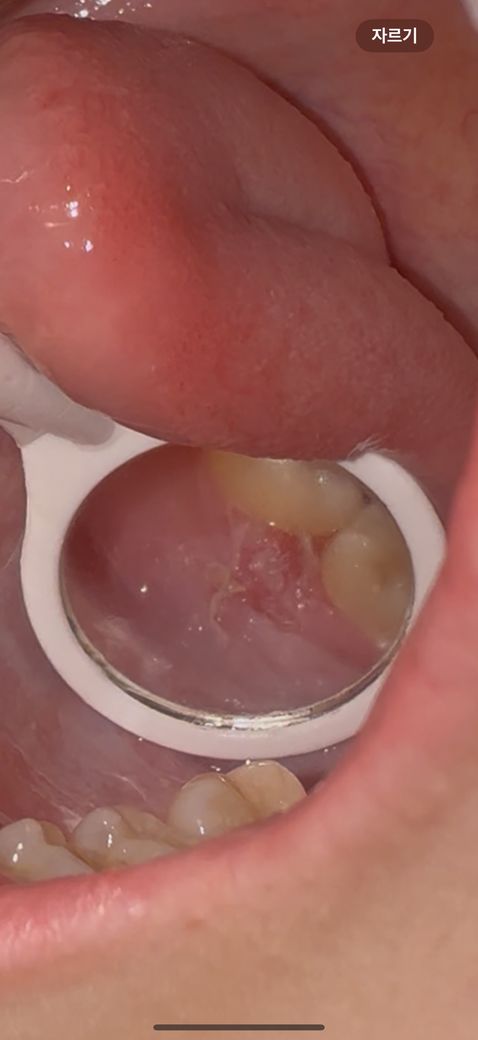

병원에 가봐야 하는 입안 병변일까요?

저번주에 치과 방문 후 .. 어금니 안쪽 잇몸에 구내염처럼 뭐가 난거같고 양치할때마다 통증이 있었습니다. 그러다 반대쪽도 났고요.(반대쪽은 통증이 덜 심함) 오늘 아침에 위쪽도 뭔가 구내염처럼 통증이 있어서

세 부위 모두 알보칠을 발랐습니다. 그랬더니 좀 더 하얘진건지 원래 저정도로 하얬는지는 모르겠어요..

백반증같은걸까요..? 치과나 이비인후과를 방문해봐야하나 고민중입니다

• 1번 째 사진